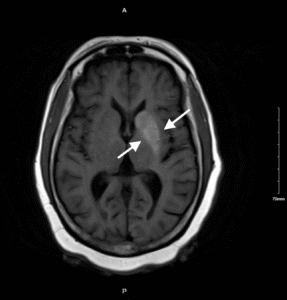

Nonketotic Hyperglycemia Hemichorea. MRI Annotated. JETem 2025